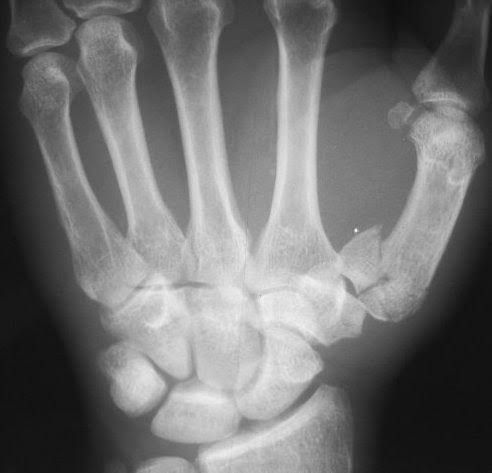

A Bennett fracture is a fracture of the base of the thumb resulting from forced abduction of the first metacarpal. It is defined as an intra-articular two-part fracture of the base of the first metacarpal bone. Despite a relatively simple appearance on radiographs, Bennett fractures are considered unstable.